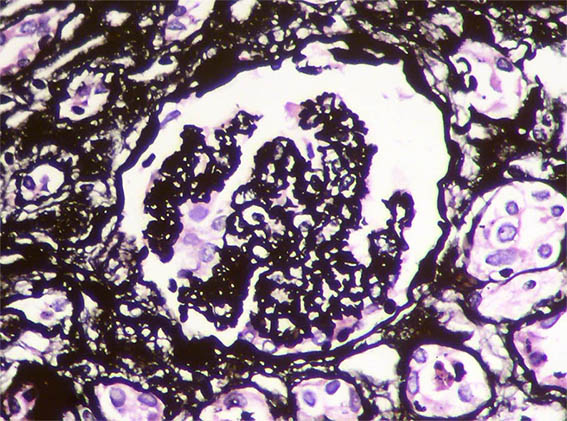

Se hace biopsia renal con impresión diagnóstica de lesión renal aguda. Ver las imágenes.

Figura 5. Plata-metenamina, X400.

Figura 6. Plata-metenamina, X400.

Figura 7. Plata-metenamina, X400. Mesangiolisis.